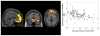

Results: Cumulative adversity was associated with smaller volume in medial prefrontal cortex (PFC), insular cortex, and subgenual anterior cingulate regions (familywise error corrected, p < .001). Recent stressful life events were associated with smaller volume in two clusters: the medial PFC and the right insula. Life trauma was associated with smaller volume in the medial PFC, anterior cingulate, and subgenual regions. The interaction of greater subjective chronic stress and greater cumulative life events was associated with smaller volume in the orbitofrontal cortex, insula, and anterior and subgenual cingulate regions.